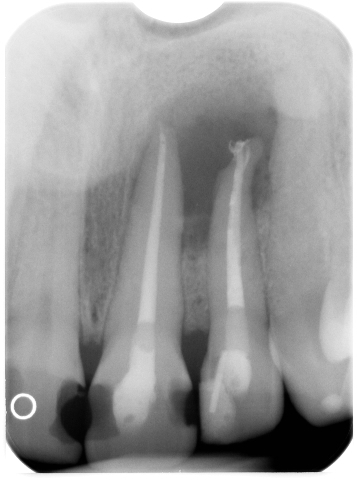

Globuli